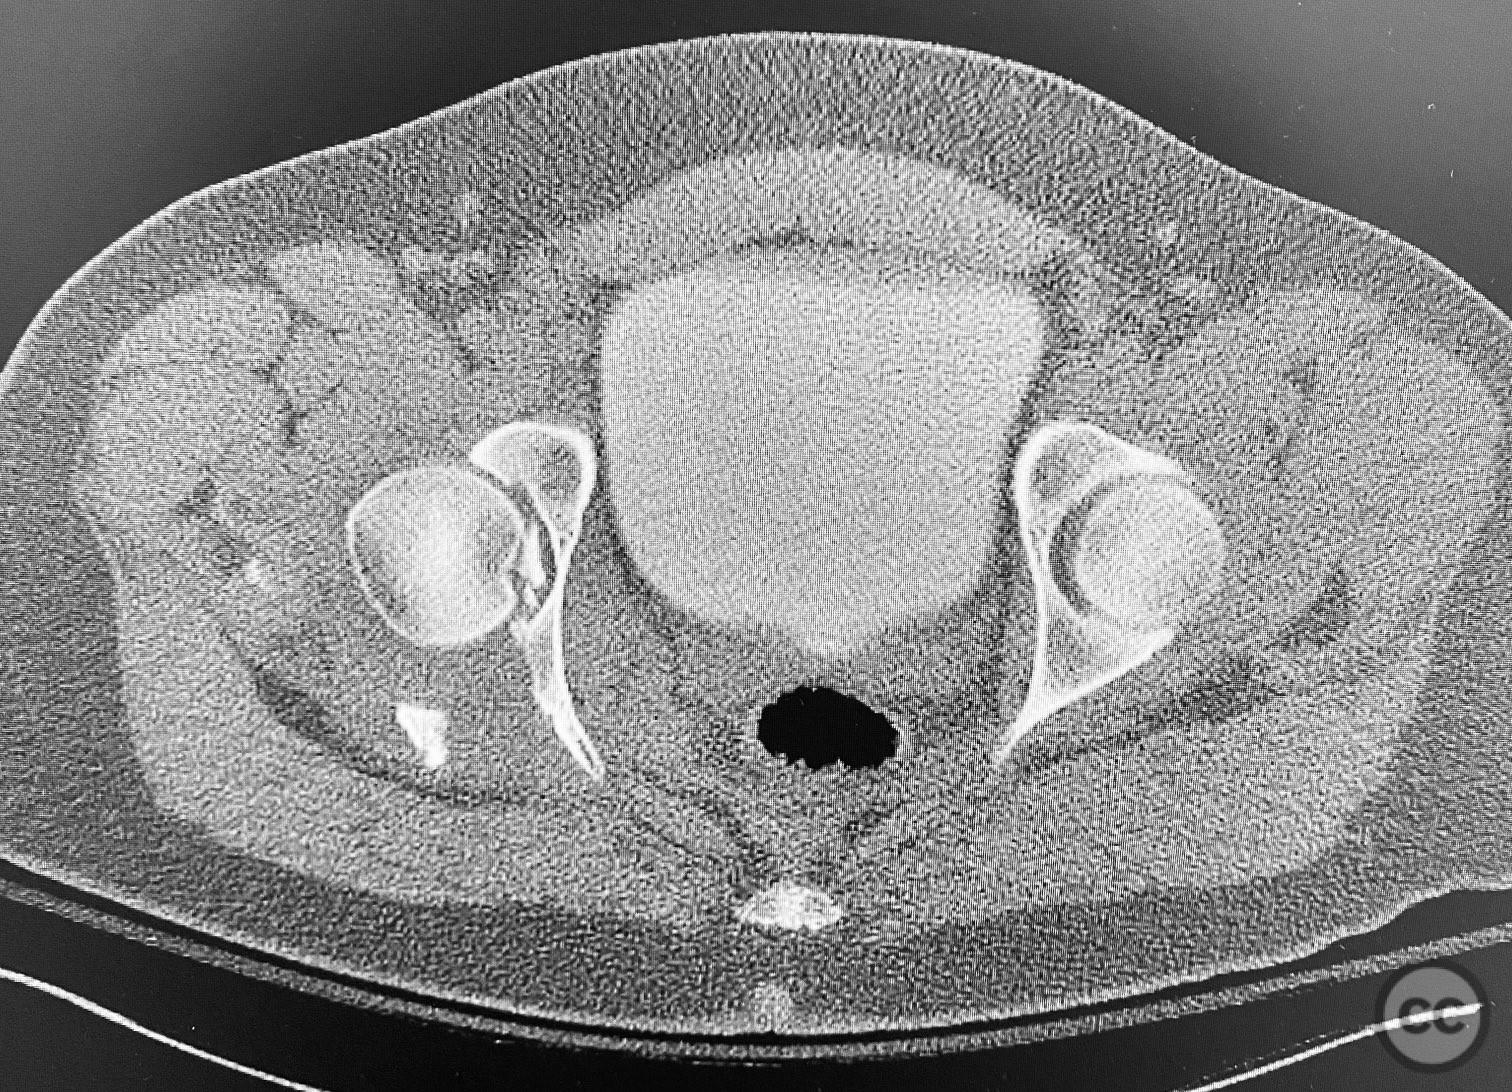

Clinical and radiological findings:  A patient sustained a comminuted posterior wall acetabular fracture-dislocation (AO/OTA 62-B1.3) involving the greater sciatic notch, with associated traumatic sciatic nerve injury. Following closed reduction, imaging demonstrated an intra-articular fragment located within the acetabular fossa (fossa acetabuli). Clinical examination revealed neurological deficit consistent with sciatic nerve involvement. Radiographs and CT confirmed the extent of comminution and intra-articular displacement.

Anatomical surgical approach:  A standard Kocher-Langenbeck approach was performed: a longitudinal incision centered over the greater trochanter, extending proximally along the posterior iliac crest and distally along the femoral shaft. The fascia lata was incised, and the gluteus maximus split in line with its fibers. The short external rotators and piriformis were identified, tagged, and released to expose the posterior column and wall of the acetabulum. The sciatic nerve was identified in the greater sciatic notch region; intraoperatively, it was found to be severely contused, displaced, and uniquely penetrated by a sharp posterior wall fragment. Neuroplasty was performed, freeing the nerve from impalement and surrounding scar tissue. The intra-articular fossa acetabuli fragment was extracted, anatomically reduced, and stabilized along with other posterior wall fragments. A spring hook plate was applied to secure the cranial wall fragment due to its size and comminution.

Intraoperatively, the sciatic nerve was found to be not only contused but also impaled by a displaced posterior wall fragment—a rare occurrence in acetabular trauma. Careful neuroplasty was required to release the nerve from direct bony penetration without further iatrogenic injury. Reduction of all articular fragments was achieved under direct visualization, with particular attention to restoring congruity of the acetabular rim and fossa. The use of a spring hook plate provided necessary buttress for the large cranial wall fragment, which could not be adequately stabilized with standard plating alone.